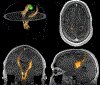

White matter fiber tracking using diffusion magnetic resonance imaging (dMRI) provides a noninvasive approach to map brain connections, but improving anatomical accuracy has been a significant challenge since the birth of tractography methods. Utilizing tractography in brain studies therefore requires understanding of its technical limitations to avoid shortcomings and pitfalls. This review explores tractography limitations and how different white matter pathways pose different challenges to fiber tracking methodologies. We summarize the pros and cons of commonly-used methods, aiming to inform how tractography and its related analysis may lead to questionable results. Extending these experiences, we review the clinical utilization of tractography in patients with brain tumors and traumatic brain injury, starting from tensor-based tractography to more advanced methods. We discuss current limitations and highlight novel approaches in the context of these two conditions to inform future tractography developments.